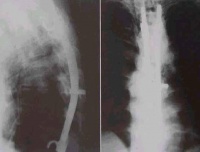

局部制动 为了缓解、防止增加畸形,避免病变扩散,减少体力消耗,及时使患者休息,颈部制动非常重要。病情较重者可采用颈托、支架或石膏保护。病情较重或已发生截瘫者,应绝对卧床。必要时还可行枕颌带牵引或颅骨牵引。枕颌带牵引适用于小儿及病期较短、肌力较弱的患者,牵引重量为1~2kg。吃饭时可将牵引暂时拿下,以便开口。颅骨牵引比较安全、舒适,而且能给予较大的牵引重量,成年人可用5kg重量,儿童酌减,畸形纠正后可使用2kg维持。牵引时可以使患者仰卧,身下垫一厚褥子,枕部放在床上,使颈椎处于过伸位。对于长期应用牵引治疗的患者应注意预防枕骨结节处发生褥疮。预防的方法是定时翻身,在枕骨结节下方垫一气圈,定时按摩并用酒精涂擦。 抗结核药物治疗 抗结核药物的应用在颈椎结核治疗中起重要作用,可提高疗效,促进病变的愈合。目前常用的一线药物有异烟肼、利福平、吡嗪酰胺、乙胺丁醇和链霉素。二线药物包括丁胺卡那霉素、卷须霉素、卡那霉素、环丝氨酸、乙硫异烟胺和对氨柳酸等。 异烟肼(INH) 具有最强的早期杀菌作用,预防药物产生耐药性最好。口服吸收快,易渗入胸腔、腹腔,脑脊液和关节液中,且能渗入细胞内,故亦能杀灭细胞内的结核杆菌。 成人每天用量300mg,分3次服用。小儿用量,每天每kg体重10~20mg。异烟肼对肝功能有损害,还有引起神经炎及精神症状,服用期间注意定期检查肝功能,大量服用可加服维生B6。 利福平(RFP) 灭菌作用最强。口服后经肠道吸收,在血液中能较长时间维持高浓度,能通过血脑屏障进入脑脊液。利福平对结核病的治疗效果较好。 成人剂量为每天450~600mg,可于清晨空腹服用,亦可分两次服用。儿童一般用量为每日每千克体重20mg。利福平有肝功能损害,胃肠道反应,皮肤反应,流感样反应等副作用。故肝功能有严重损害及胆道有梗阻的患者忌用,老年人、儿童、营养不良者慎用。 吡嗪酰胺(PZA) 具有对酸性环境中细胞内结核菌群的特殊的灭菌作用。PZA和RFP联合则具有最强的灭菌作用。成人每天用量1~1.5g,分~3次口服。中毒作用为肝功能损害,并能引起关节疼痛。 乙胺下醇(EMB) 抗结核作用较强,可弥漫到人体各组织中。成人用量为每天750mg,一次服完以便获得高峰血浓度。副作用有视力障碍。当早期出现色觉障碍时即应停药。 链霉素(SM) 属抑菌药,仅对细胞外的结核杆菌有杀灭作用。口服不易吸收,肌肉注射可以渗入到各种组织中,但不能或很少通过血脑屏障。长期服用可有听神经损害和肾功能损害,注意定期检查肾功能。成人使用剂量,每天1g,分两次肌注。儿童用量为每天15~30mg/kg体重。 抗结核药物的使用原则是早期、足量、联合、规律用药。目前临床所用的联合用药方案很多,有人研究表明:INH、RFP和PZA三药联合使用能发挥各自作用和协同作用,作用于三种不同代谢菌群和细胞内外菌群,药物在不同pH值的情况下达到杀菌和灭菌作用,从而大大缩短治疗时间。疗程一般为6~9个月。用药期间注意观察毒副反应。定期检查并及时调整。 手术治疗 在抗结核药物的控制下,及时彻底地清除结核病灶,可以大大缩短疗程,预防畸形或截瘫的发生,大大提高了颈椎结核的治愈率。同时应强调手术适应证,不应滥用手术。